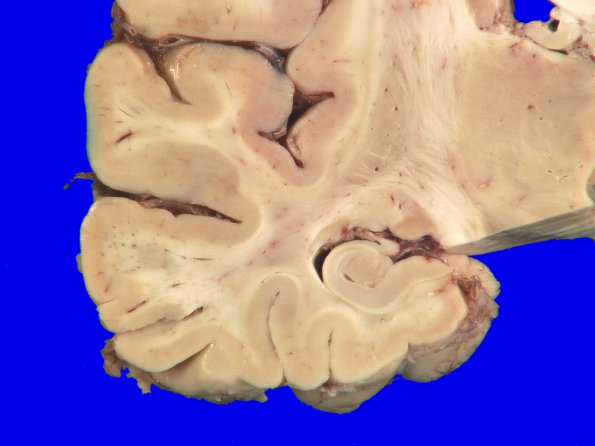

Higher magnification of hippocampus and temporal lobe showing normal size and substructure.